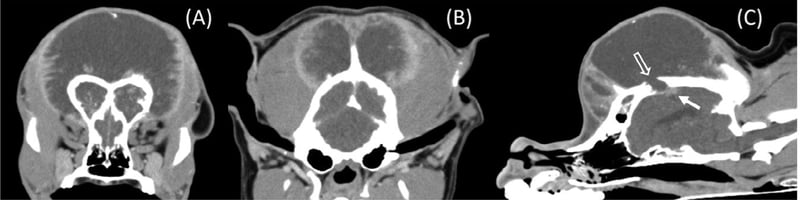

- Canine

Canine